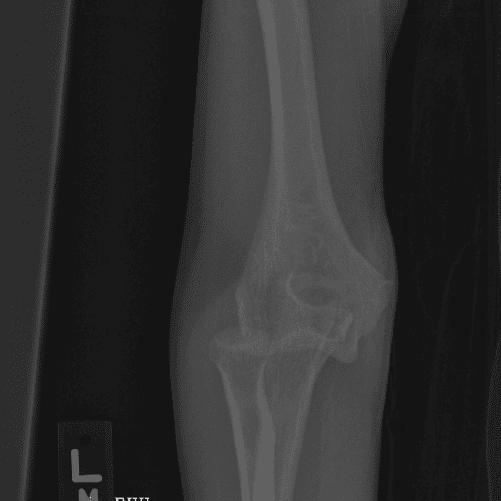

Simulates call by including subtle or difficult cases and some normals.

40 cases